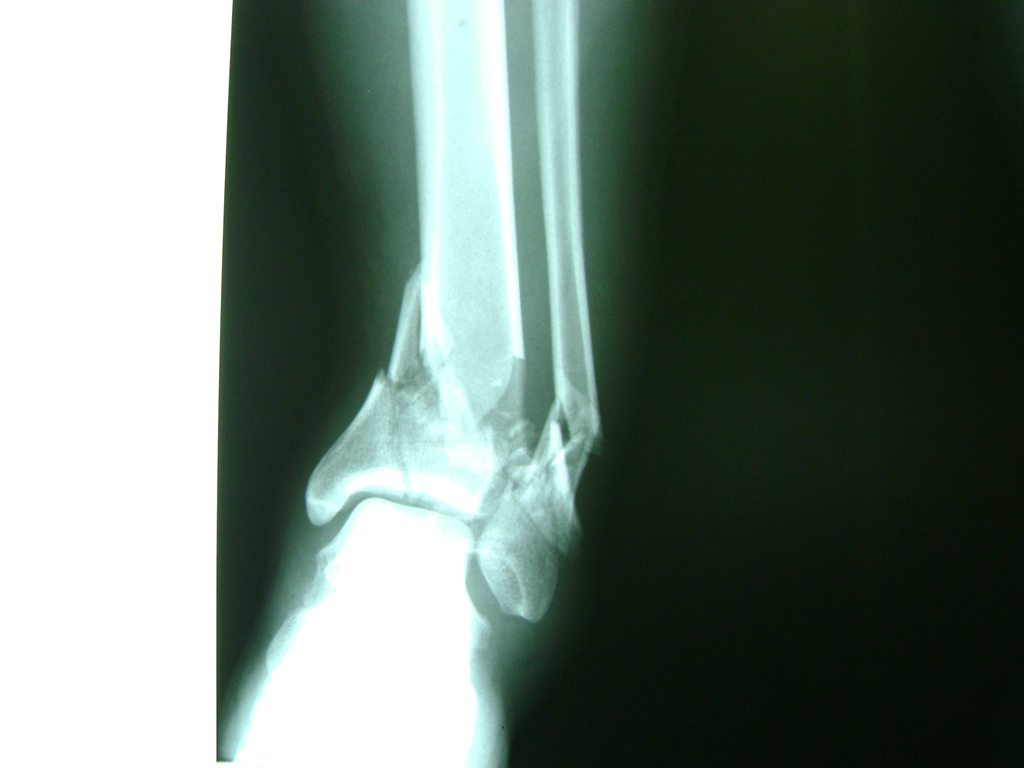

Una fractura de tobillo es la rotura de uno o más de los huesos del tobillo. Estas fracturas pueden ser:

Algunas fracturas de tobillo pueden requerir cirugía si:

- Los extremos de los huesos están desalineados entre sí (desplazados).

- La fractura se extiende hasta la articulación del tobillo (fractura intra-articular).